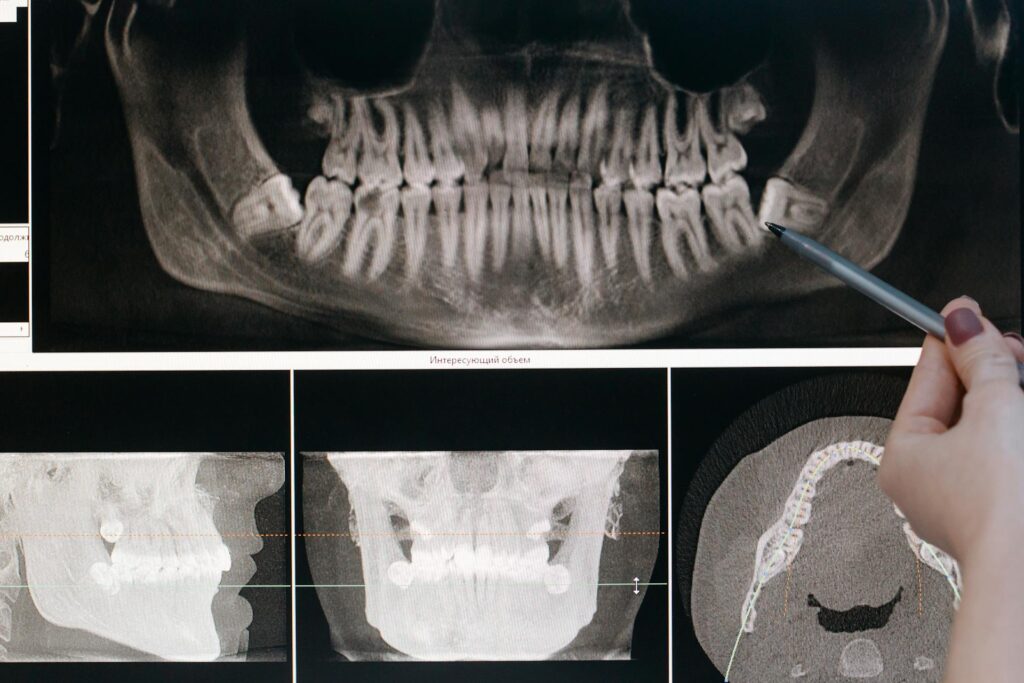

El escaneo intraoral es el primer paso en la planificación digital de tratamientos con alineadores. Si el escaneo no es preciso, los modelos digitales no serán fiables, lo que conlleva retrasos, retrabajos y posibles errores clínicos.

Una impresión digital ortodóncica precisa y correcta permite desarrollar alineadores que se ajustan perfectamente y, además, optimizan también el movimiento dental. Conocer y aplicar un protocolo adecuado es clave para garantizar datos fiables y que sean predecibles.